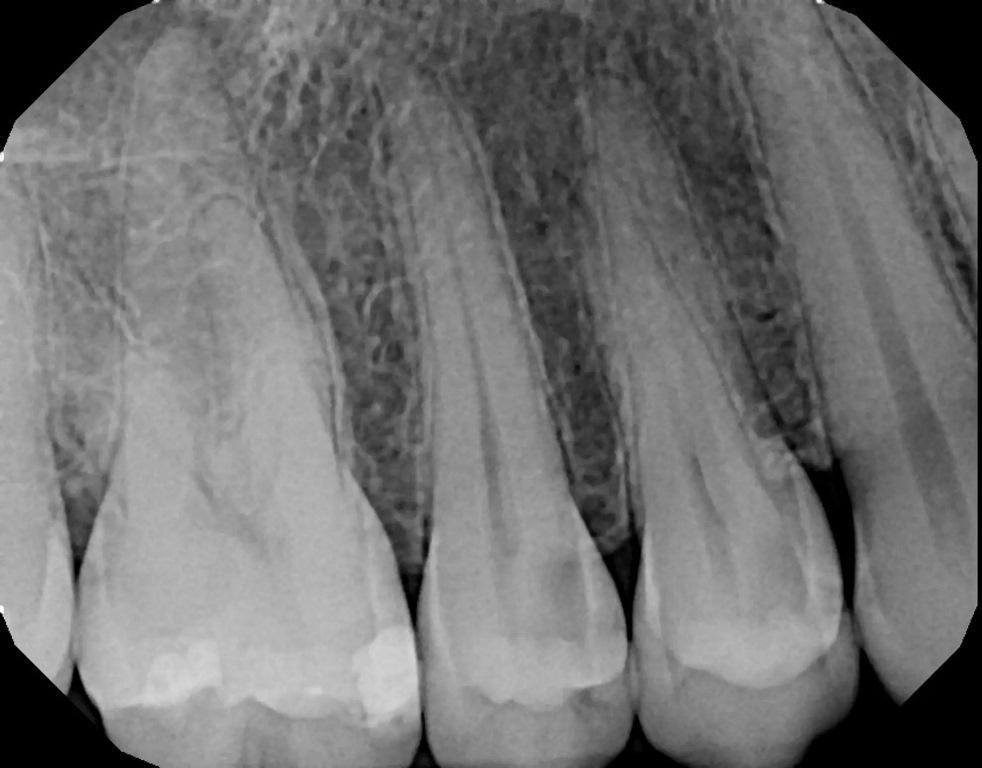

29-летняя пациентка обратилась с жалобой на чувствительность в правом квадранте верхней челюсти и попросила дать повторное заключение о возможной необходимости эндодонтического лечения, которое в связи с глубоким кариесом рекомендовал ее предыдущий стоматолог. Она сообщила о чувствительности второго премоляра к горячему и холодному, а также о сохраняющейся чувствительности второго премоляра к холоду. Была сделана периапикальная рентгенограмма, которая показала кариес на зубах №15 и 14 с мезио-окклюзионной стороны, а у зуба №15 в непосредственной близости от пульпы. Периапикальной патологии отмечено не было (фото 18). Пациентка была проинформирована о возможной необходимости эндодонтического лечения и о том, что это будет определено после удаления кариеса и в случае обнаружения обнажения пульпы. При отсутствии контакта с пульпой можно провести лазерное удаление пульпы и восстановить зуб, но более поздние проявления повышенной чувствительности зубов могут указывать на необходимость эндодонтического лечения. Пациентка согласилась продолжить лечение.

Фото 18: Первичная периапикальная рентгенограмма, демонстрирующая кариес с мезио-окклюзионной стороны зубов №15 и 14 и отсутствие периапикальной патологии.